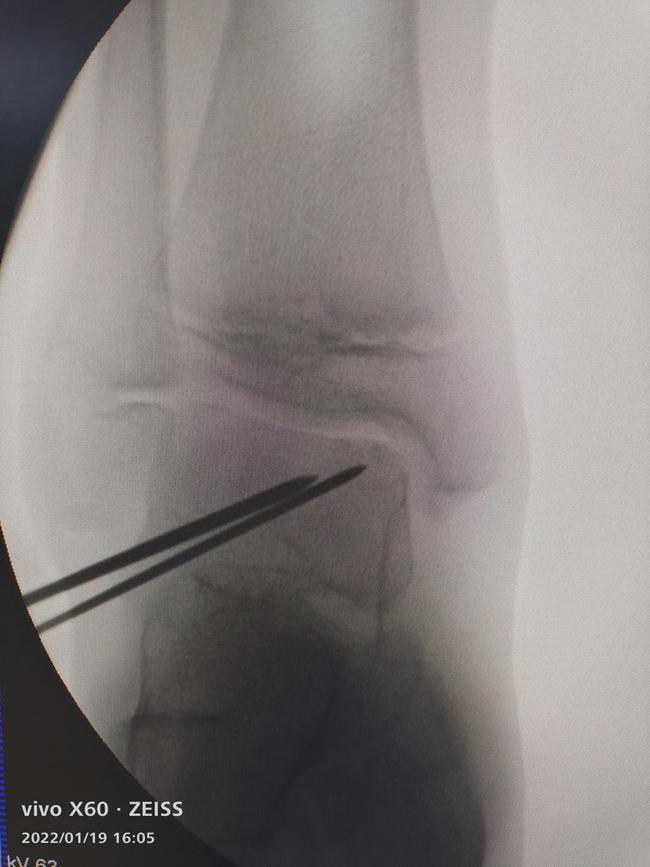

- 病灶小(<8mm),损伤2、3级,可通过:骨髓刺激技术:微骨折/逆向钻孔治疗(图3、图4)

图4 C臂机下定位逆行钻孔治疗距骨软骨损伤

手术治疗可以切开或关节镜下手术,我科通常选用关节镜下检查病变情况,儿童青少年病变程度不严重多采用镜下微骨折或钻孔手术。